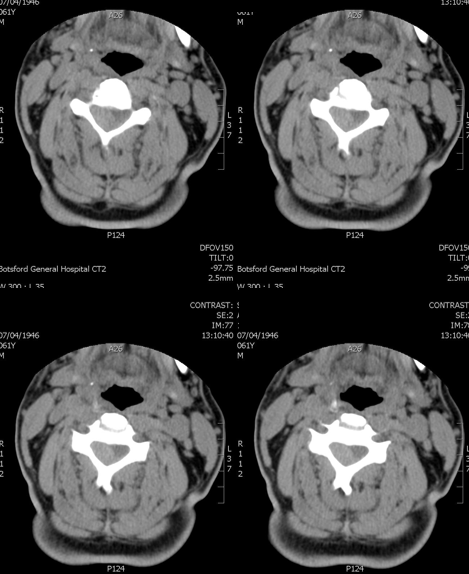

✨Up Next in our Member Spotlight Series - featuring Dr. Rocky Saenz! His passion for education has inspired numerous medical students and radiology residents. Dr. Saenz has made significant strides for DOs and radiologists, enhancing their recognition in the medical field.